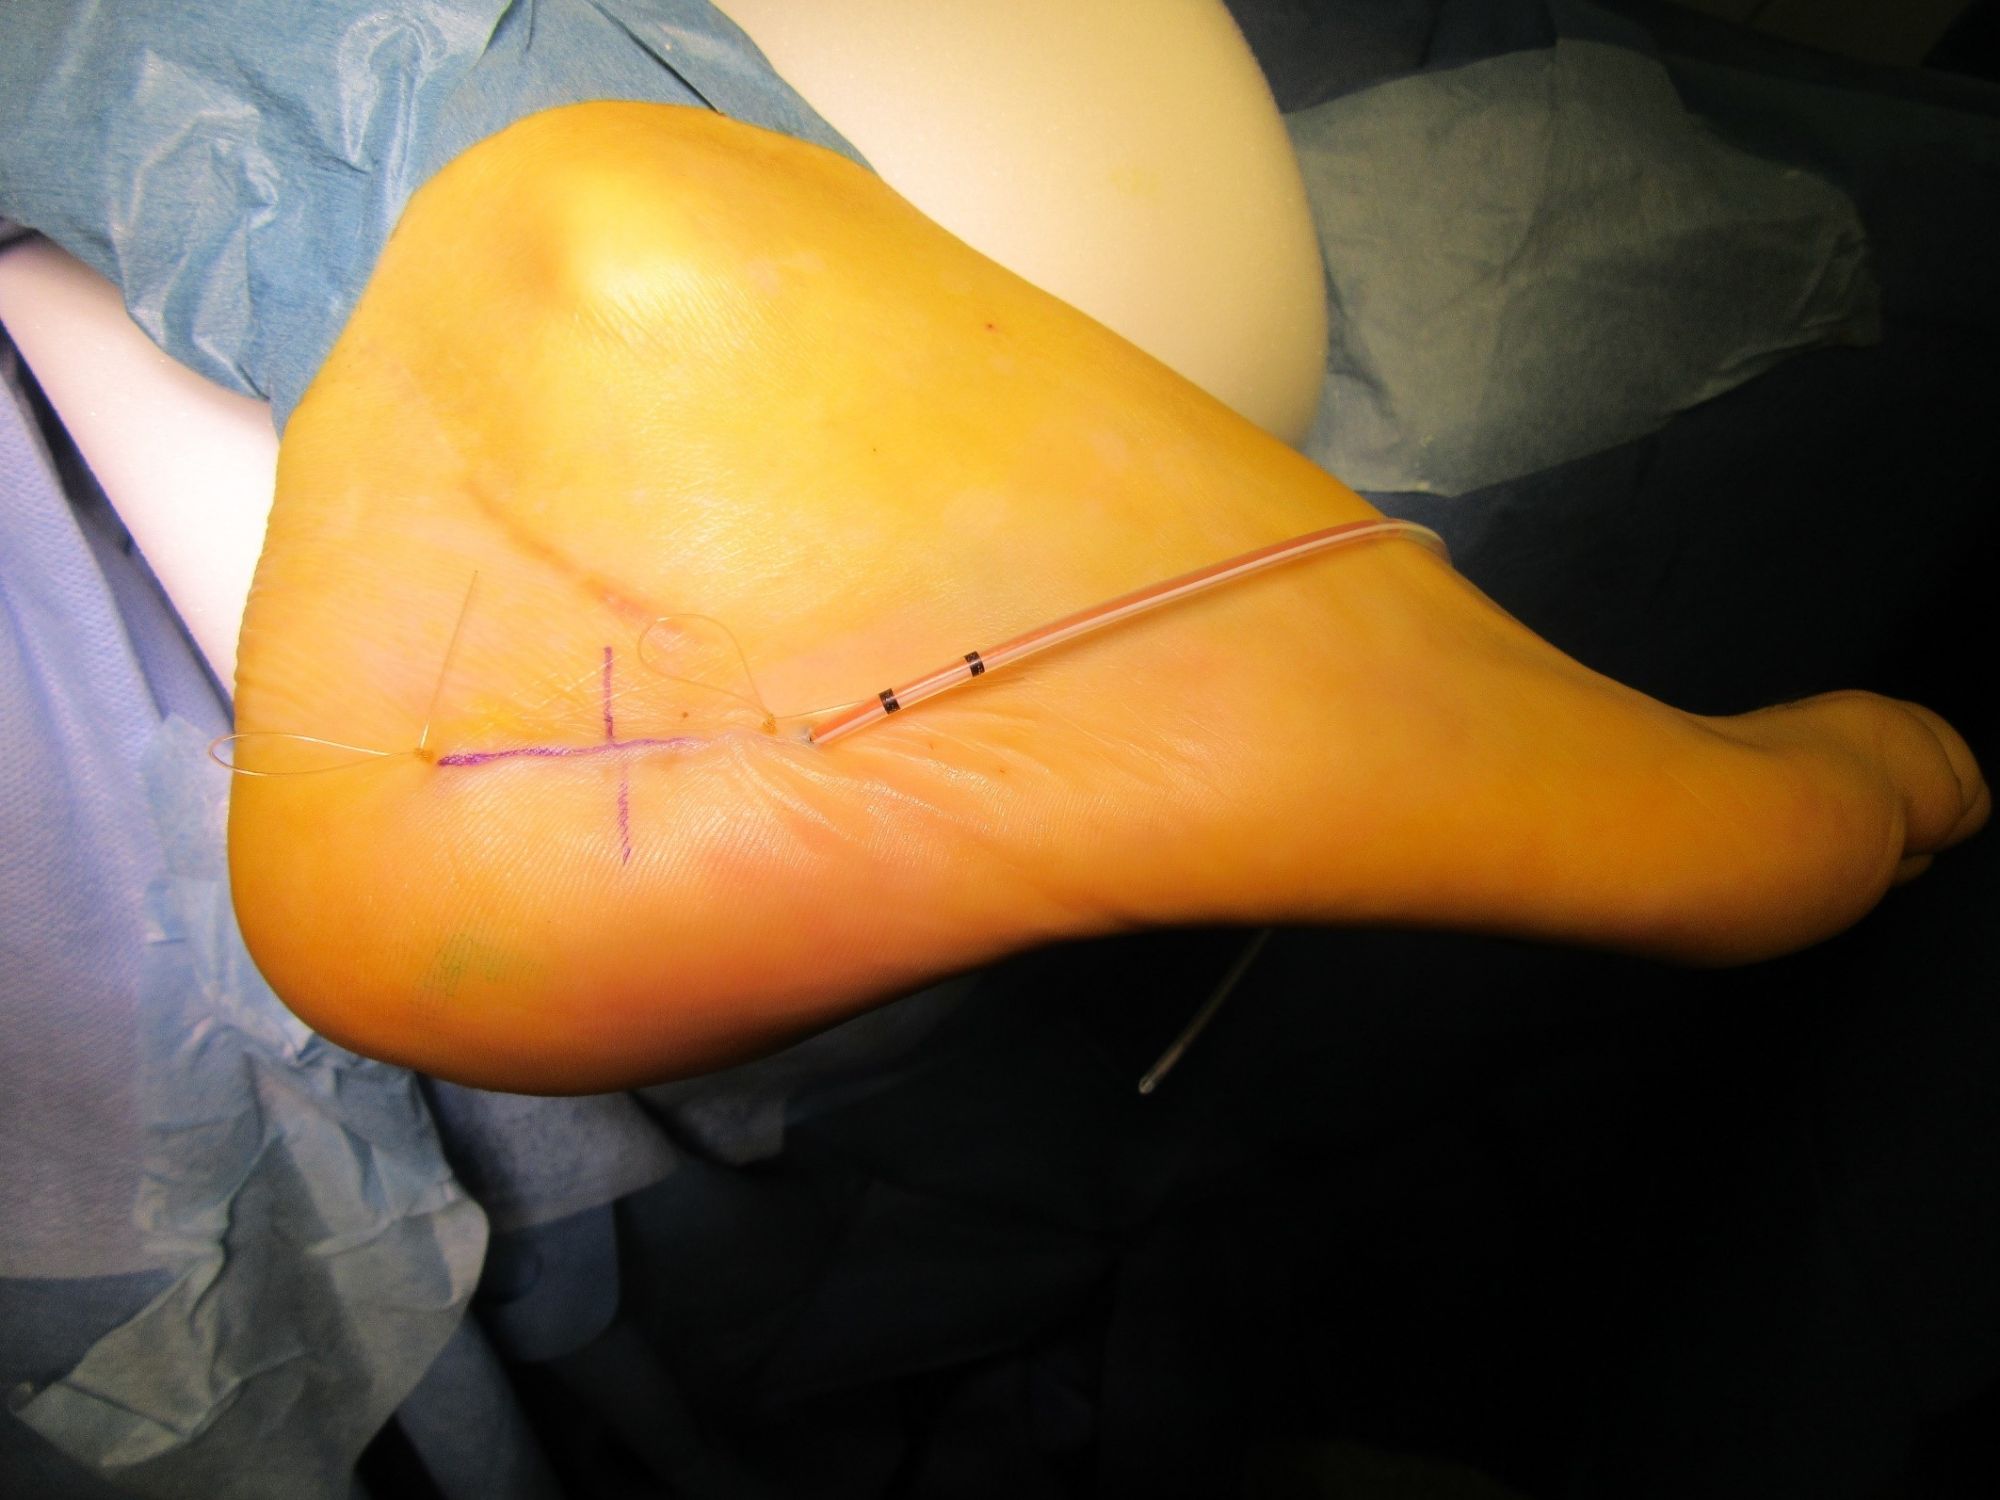

Abbildung 4: OP-Situs

Darstellung der Ausrissverletzung, Refixation durch Anker.

Zum Lesen der Bildbeschreibung und zur Vollansicht bitte das Bild anklicken. Bild: Manfred Thomas.

Abb. 7a: Markieren des Schmerzareals am Plantarfaszienursprung.

Abb. 7b: Perforation der markierten Einführungspunkte an der Fersenhaut und Einführen der TOPAZ Sonde.

Abb. 7c: Einführen der TOPAZ Radiofrequenz Sonde.